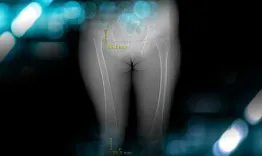

The goals of this clinical case are to discuss the classifications and therapeutic options for a hip dysplasia in a middle aged patient

Management of a hip dysplasia in a middle-aged woman

Filippo Randelli, Giuseppe Fedele